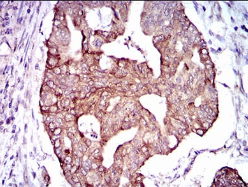

PDE1B Mouse Monoclonal antibody[5C4A]

IHC    1/200 - 1/1000